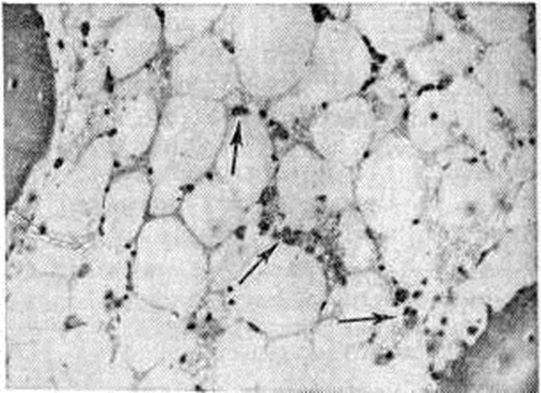

При микроскопическом исследовании наиболее характерны изменения органов кроветворения, начальные признаки поражения которых обнаруживаются в латентном периоде задолго до ярких клинические, проявлений острой Лучевая болезнь В лимфатических, узлах в первые часы после облучения можно видеть распад лимфоцитов, особенно в центральной части фолликулов, то есть в зоне расположения В-лимфоцитов; несколько позже выявляются изменения в паракортикальном слое (зона Т-лимфоцитов). В период разгара заболевания на фоне резкой гиперемии различимы в основном элементы стромы лимфатических, узла и плазматические клетки. Аналогичные изменения наблюдаются в миндалинах, селезёнке, групповых фолликулах (пейеровых бляшках) и солитарных фолликулах желудочно-кишечные тракта. В костном мозге быстро развивается аплазия: к третьим суткам в нем остаётся, по данным некоторых авторов, лишь около 10% клеточного состава, что объясняется усиленным выбросом в периферическое русло зрелых форм, прекращением деления и распадом клеток (интерфазная гибель); в последующем митотическая активность на некоторое время возобновляется, но делящиеся клетки погибают в процессе митоза. Быстрое и значительное клеточное опустошение сопровождается как бы викарным полнокровием сосудов костного мозга с разрывами сосудистых стенок и образованием полей кровоизлияний. В периоде разгара острой Лучевая болезнь в костном мозге почти не остаётся обычной кроветворной ткани, видны преимущественно элементы стромы и плазматические клетки (рисунок). Поражение лимфоидной ткани и костного мозга приводит к снижению иммунобиологический реактивности организма и создаёт благоприятные условия для развития разнообразных осложнений, главным образом аутоинфекционного характера.